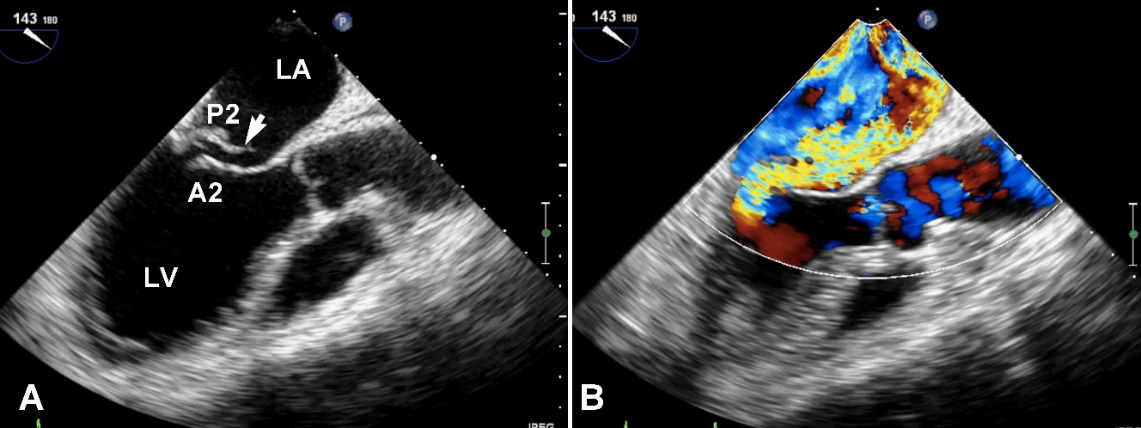

反流束最窄的部分,称为“缩流颈(vena contracta)”,可以通过测量缩流颈的直径(图21)来判断反流的程度,当直径≥5.5mm时,与心导管测量的重度反流相关性很好。如果使用7mm作为重度MR的截断值会更有帮助,此时特异性强,但敏感性大幅下降。

图21缩流颈的测量食管中段四腔心切面,反流束基底部宽度与二尖瓣反流的严重程度相关。

反流束的方向也很重要,其不仅仅是病因学的线索,也是严重程度的一个征象。中心性反流可由瓣环扩张或心室功能不全引起,偏心性反流(图22)常常由二尖瓣结构本身异常引起的,偏心性的贴壁反流束应该认为是中度以上的。

图22偏心性二尖瓣反流。中食管四腔心切面二尖瓣彩色多普勒血流成像,可见重度MR沿左房内侧壁走行达房顶部。